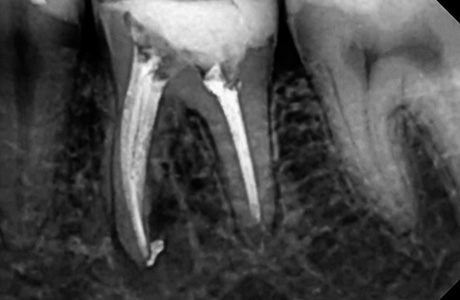

До и после лечения

Пациент обратился к нам с жалобами на длительные боли ноющего характера. Боль в области 36 зуба усиливалась при накусывании. После проведения осмотра и рентген-диагностики врачом Афанасьевой Юлией Евгеньевной был поставлен диагноз — обострение хронического периодонтита 36 зуба.

В ходе лечения врач провёл работы:

- проведено эндодонтическое лечение с применением коффердама;

- постоянная пломбировка 4-х корневых каналов;

- временно восстановлена коронковая часть 36 зуба;